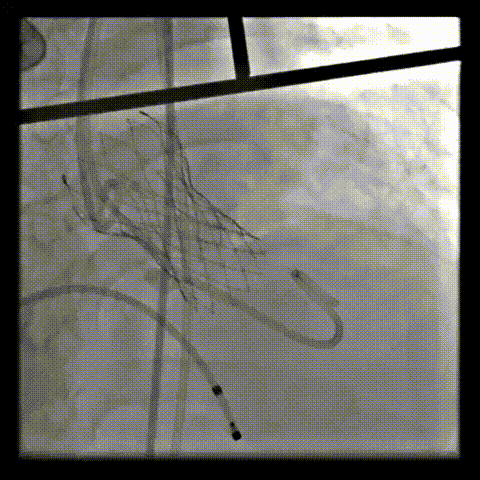

术中影像

根部造影可见返流,23mm球囊预扩张

无窦侧严重钙化及融合影响,

瓣膜(AV29)释放不稳出现反复上跳,2次回收尝试

重新定位释放,

钙化及融合挤压导致瓣膜(AV29)下滑位置偏深

第三次回收重新定位

工作位造影位置良好,完全脱钩释放瓣膜(AV29)

考虑支架腰部挤压,23mm球囊充分后扩后形态良好,

极微量瓣周漏